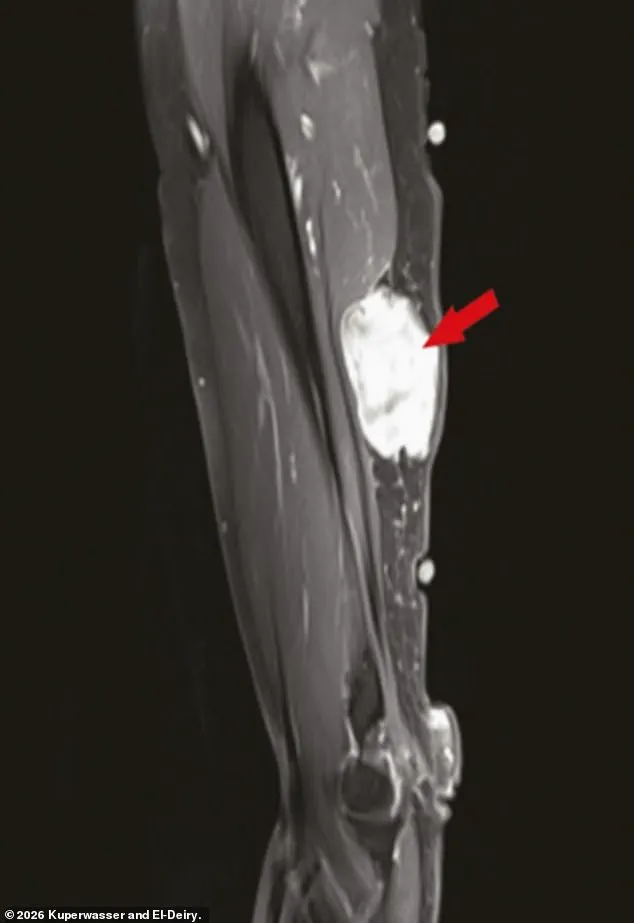

The study itself examined a range of data, including 333 cases of cancer diagnosed in the weeks and months following vaccination or booster shots.

Notably, many of the cases involved tumors growing near injection sites in the arm, a detail that has raised questions about possible localized immune responses.

However, the researchers were quick to emphasize that their findings did not establish a causal link between the vaccines and cancer.

Instead, they suggested that further research was needed to understand any potential biological mechanisms that might explain the observed patterns.